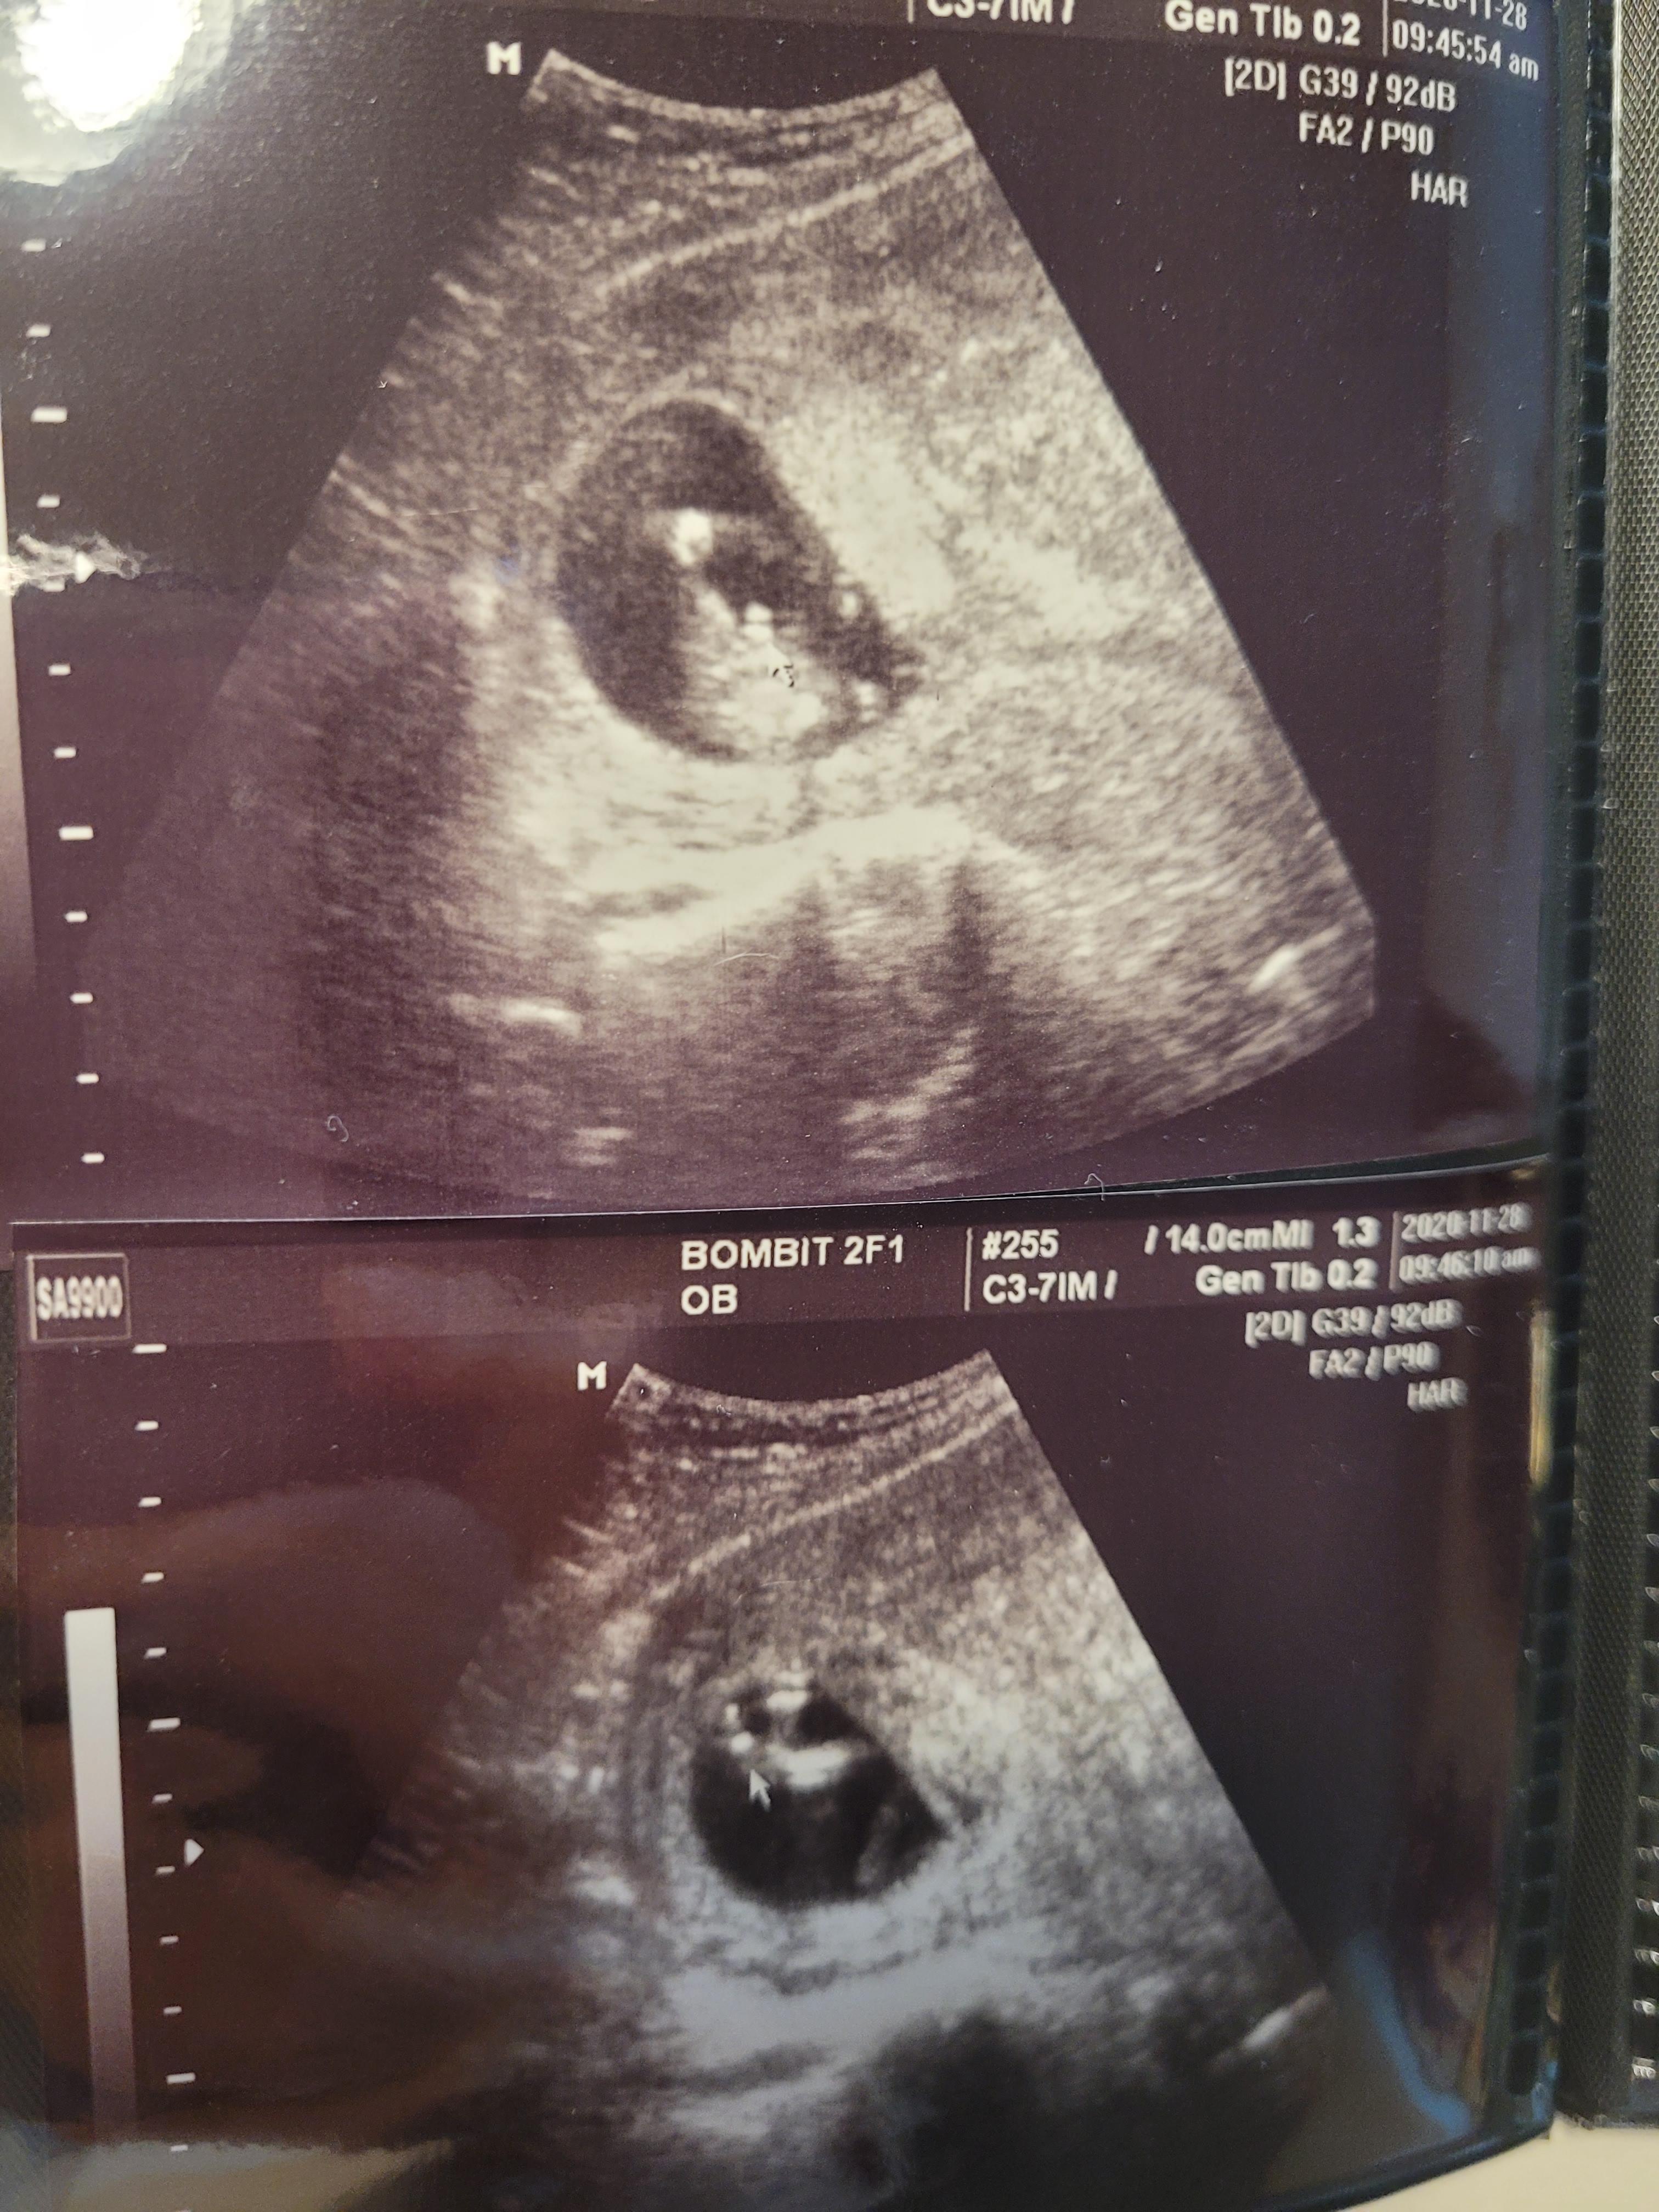

다만, 약간의 피고임이 있었던게 흘러나온것 같고,

초음파 상에 피가 약간 고여있는게 보인다고 하시면서

피고임이 흐르면 양수가 오염될수 있으니 입원해서 2~3일 항생제 맞고 가는게 어떠냐고 하셨어요.

이번 초음파를 보시더니 다리 사이에 무언가가 너무나 잘 보인다고 하시며

사진으로 캡쳐도 해주시고요ㅎㅎ

그렇게 저는 아들맘이 되었어요^^